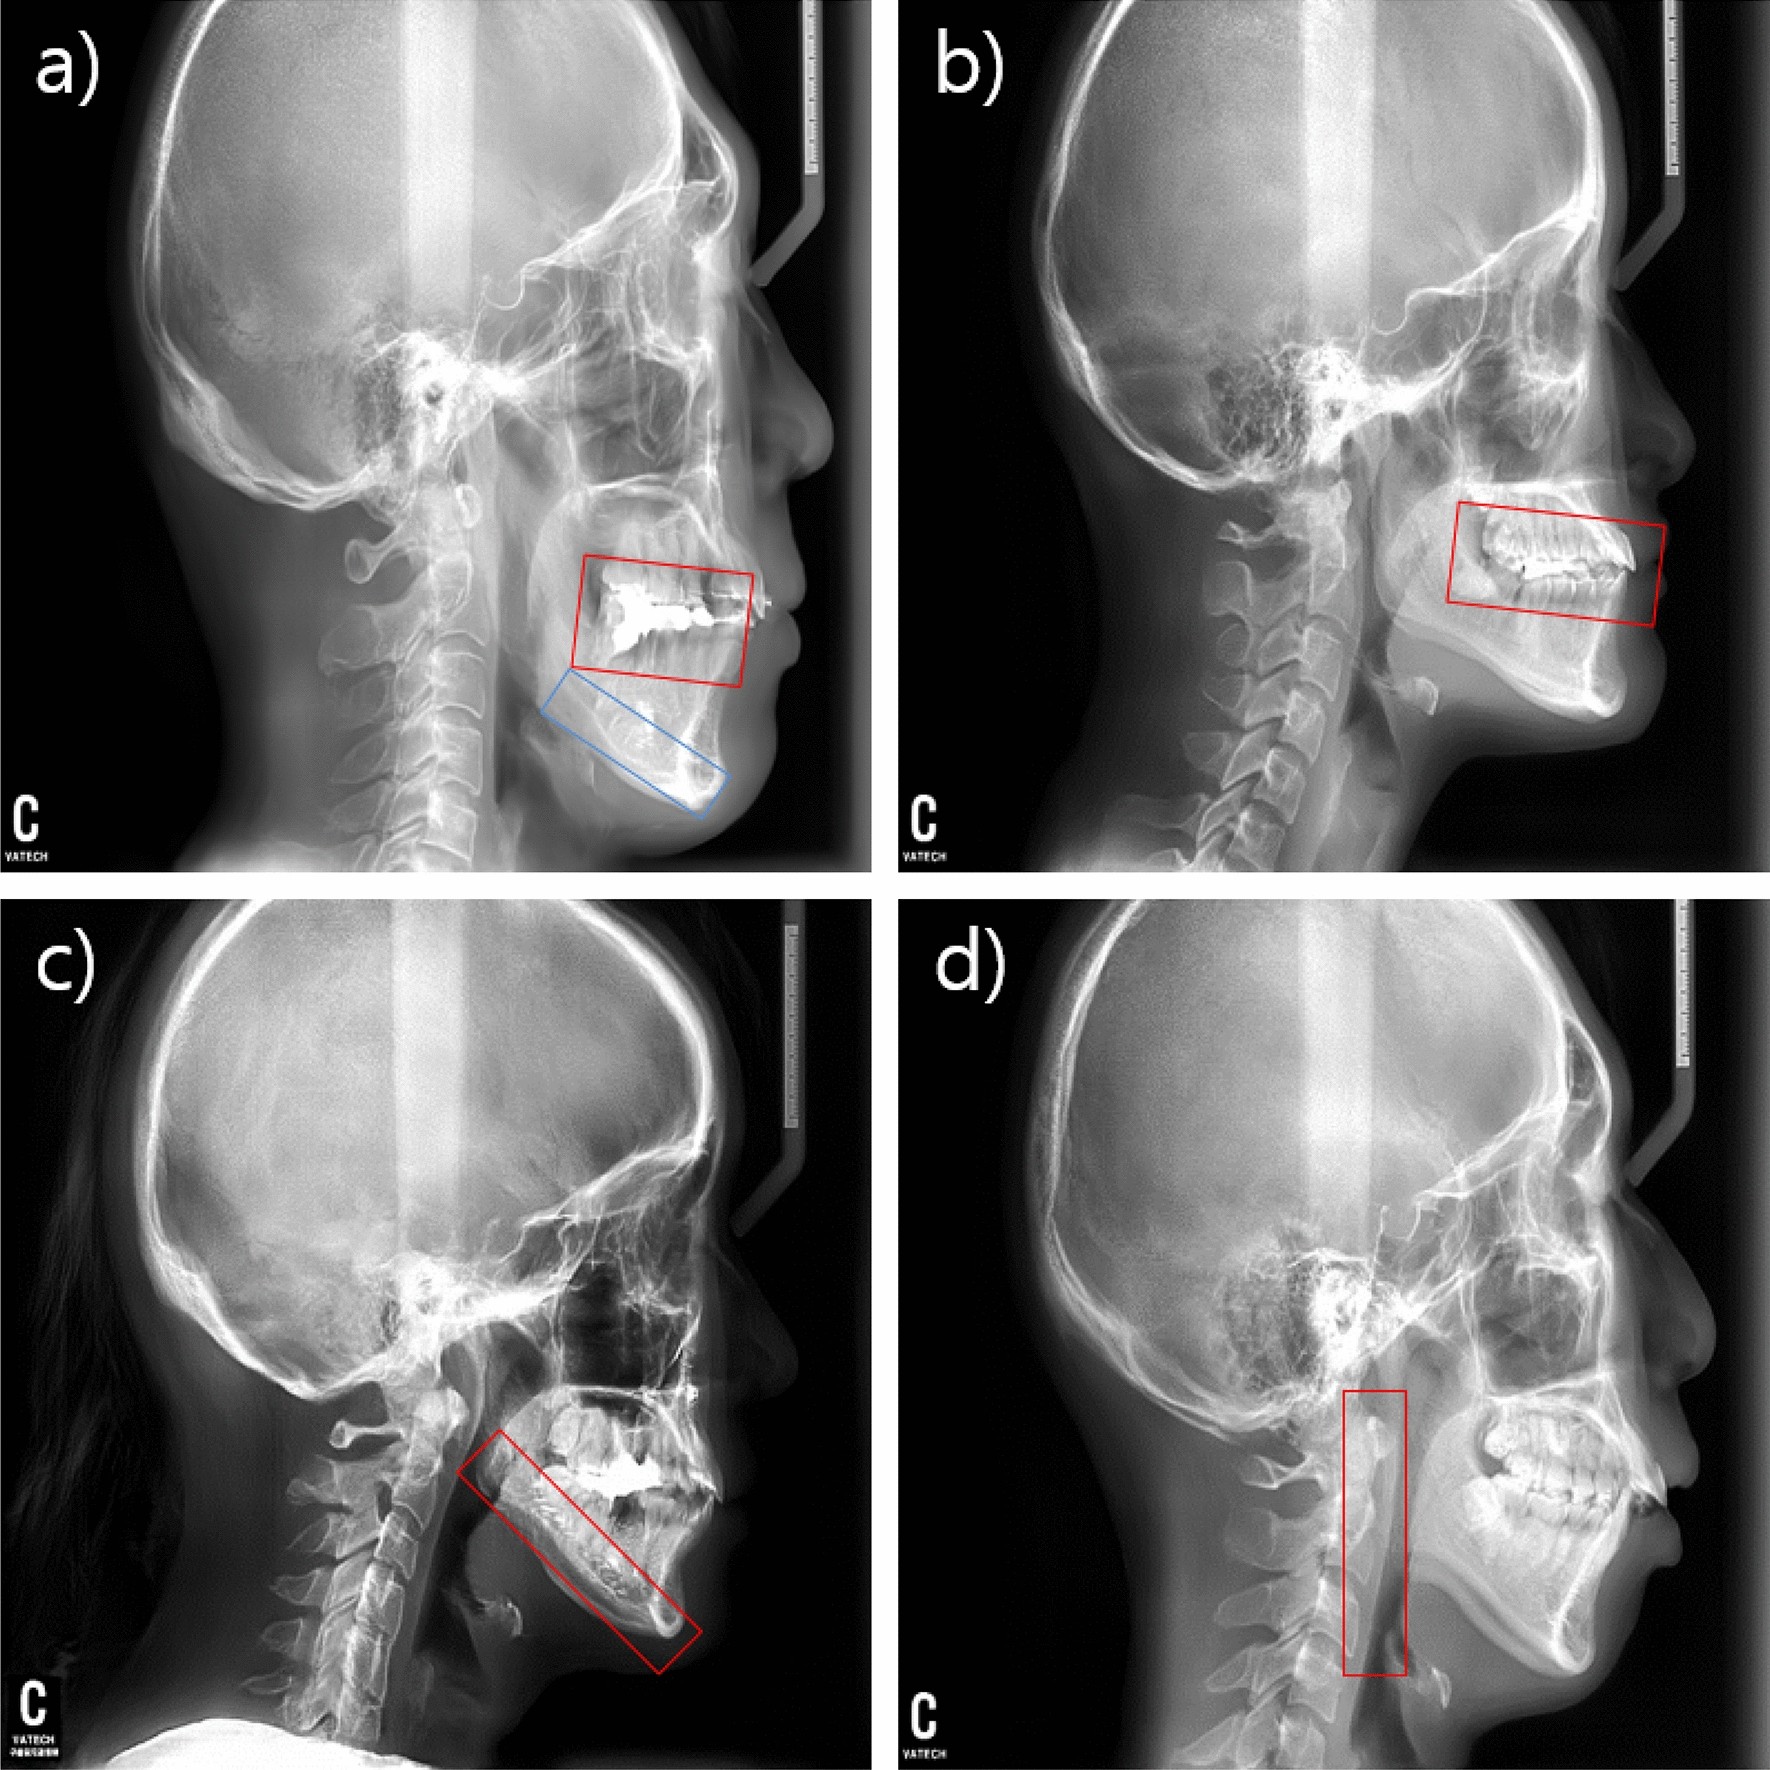

Figure 5

Regions of interest for the most prominent difference features. (a) Overlapped teeth region (red color) and radiopaque line (blue color). (b) Occlusal-plane point. (c) Cortical line of the mandibular. (d) Ramal planes.